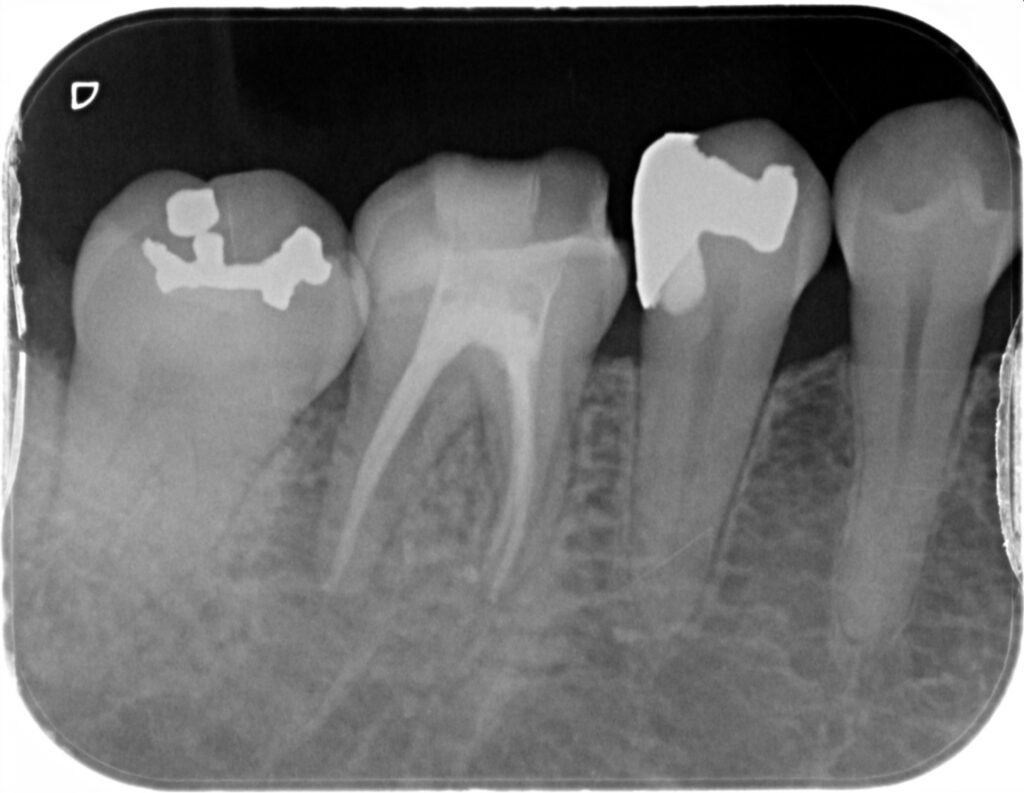

診察とレントゲン検査を行ったところ、右下6番は神経の治療(根管治療)が必要な状態で、歯の内部で起きた感染が原因となり、歯ぐき側へ膿が出て腫れにつながっている状況が疑われました。

当日は痛みが強かったため、即日で根管治療を開始しました。治療後には、腫れが落ち着いてくる様子も見られ、症状の改善が期待できる状態になりました。治療の経過は、症状の変化だけでなく、必要に応じてレントゲンでも確認しながら進めていきます。